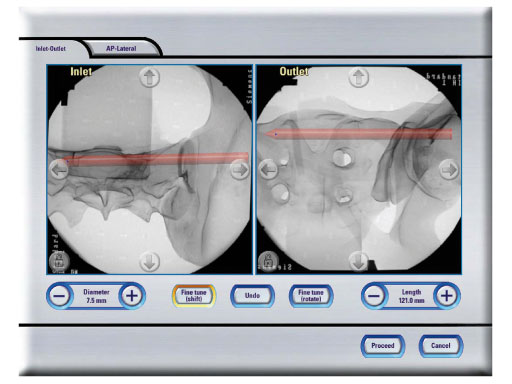

The Posterior Pelvic Ring Fixation Module guides surgeons through the complex anatomy of the pelvis during a screw fixation of the posterior pelvic ring. An easy-to-use interface enables intuitive planning and insertion of sacroilliac screws, based on multiple intraoperatively obtained C-arm images. The display simultaneously shows the surgical instruments in all relevant views (inlet, outlet, AP and lateral), and the surgeon is safely guided to the desired target position. This virtual fluoroscopy also substantially reduces radiation time, and is particularly useful for C-type fractures, according to the Mller AO Classification.